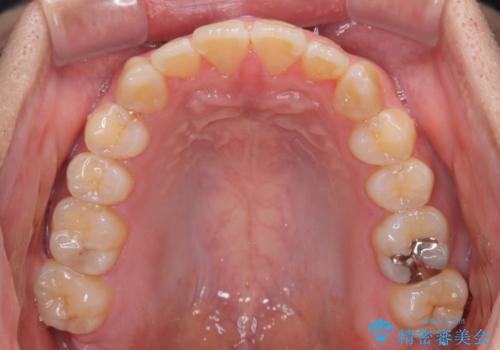

オープンバイトをインビザラインで矯正治療

- 前歯の開咬を気にして来院された患者様です。

開咬の治療は、前歯を閉じるように動かすとともに、上下臼歯を圧下(骨内にめり込ませる)させることで進めて行きます。

インビザラインは臼歯の圧下を効果的に行えるため、インビザラインを用いて矯正治療を行うこととしました。